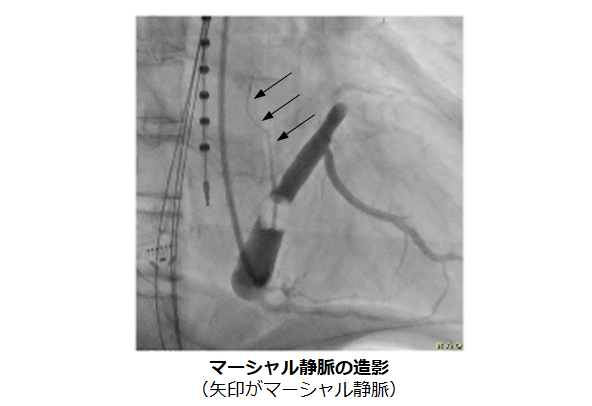

マーシャル静脈という僧帽弁輪付近にある細い血管に高濃度エタノールを注入することで心房を焼灼します。これを行うことで僧帽弁輪アブレーションの成功率が飛躍的に向上することが当院のデータでも示されています(※1)。エタノールによる焼灼は僧帽弁輪以外にも肺静脈や心臓周囲の自律神経をも焼灼すること、術後に心房頻拍が発症することも抑制する効果も示されており、心房細動アブレーションの成功率向上に寄与することが期待されています。

※1 J Cardiovasc Electrophysiol. 2021;32:2116-2126